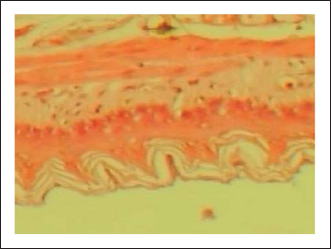

The gastric tissue slides were examined under a microscope for morphological changes such as hyperemia, hemorrhage, edema, necrosis, inflammatory changes, distortion, erosion, and ulcers caused by the destructive effects of indomethacin on stomach tissues. No pathological changes were observed in the normal control group (Fig. 1). Rats in the ulcer control group showed significant damage to the surface epithelium, necrotic areas penetrating the mucosal layer, and severe edema of the submucosal layer. Additionally, there was congestion with infiltration of inflammatory cells (Fig. 2). Histological results revealed that the treated rats with ranitidine had less protection of the gastric lining due to mild infiltration of leucocyte and edema in the submucosal layer, in addition to less disruption in both the superficial and deep mucosal layers. Treatment doses (300, 400 and 500 mg/kg) with P. farcta extract. Groups treated with P. farcta extract (300 and 400 mg/ kg) showed mild infiltration of inflammatory cells, edema, or significant disruption of the deep mucosa (Figs 5 and 6) while, P. farcta extract group (500mg/ kg) prevented histological changes and showed no infiltration of inflammatory cells, edema, or significant disruption of the deep mucosa (Figs 3, 4 and 7).

Fig. 2. Normal control group received distilled water, No pathological changes were observed.